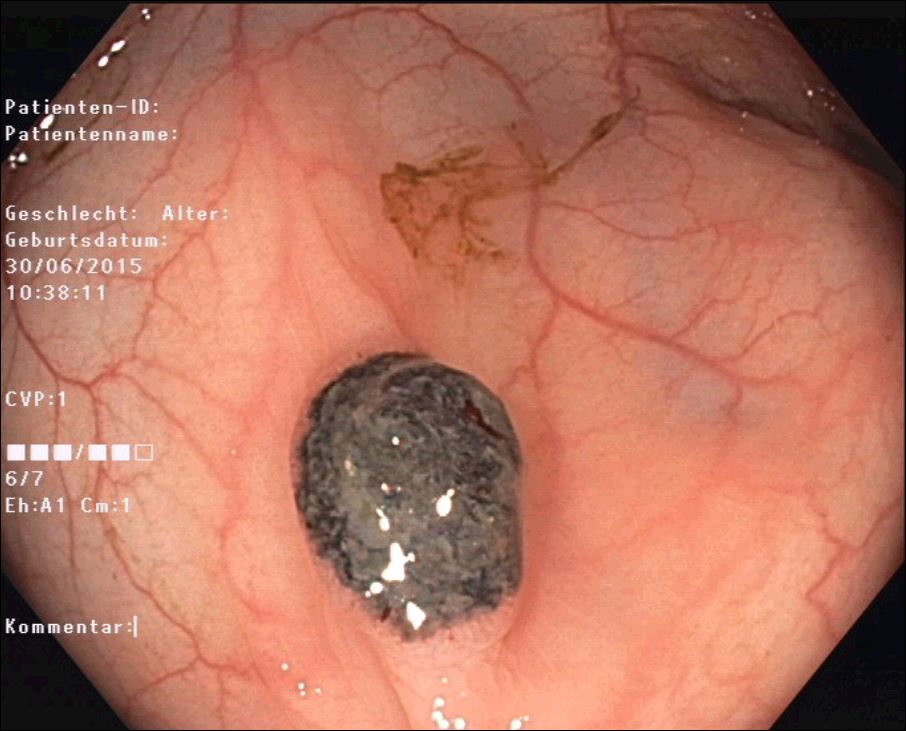

Unfortunately, the following endoscopy revealed multiple metastases in the stomach, duodenum and colon (Fig. 4-6) that endoscopically and histologically confirmed as metastasis of a malignant melanoma.

Figure 5: Polypoid melanoma metastasis in the stomach. Typical black color.